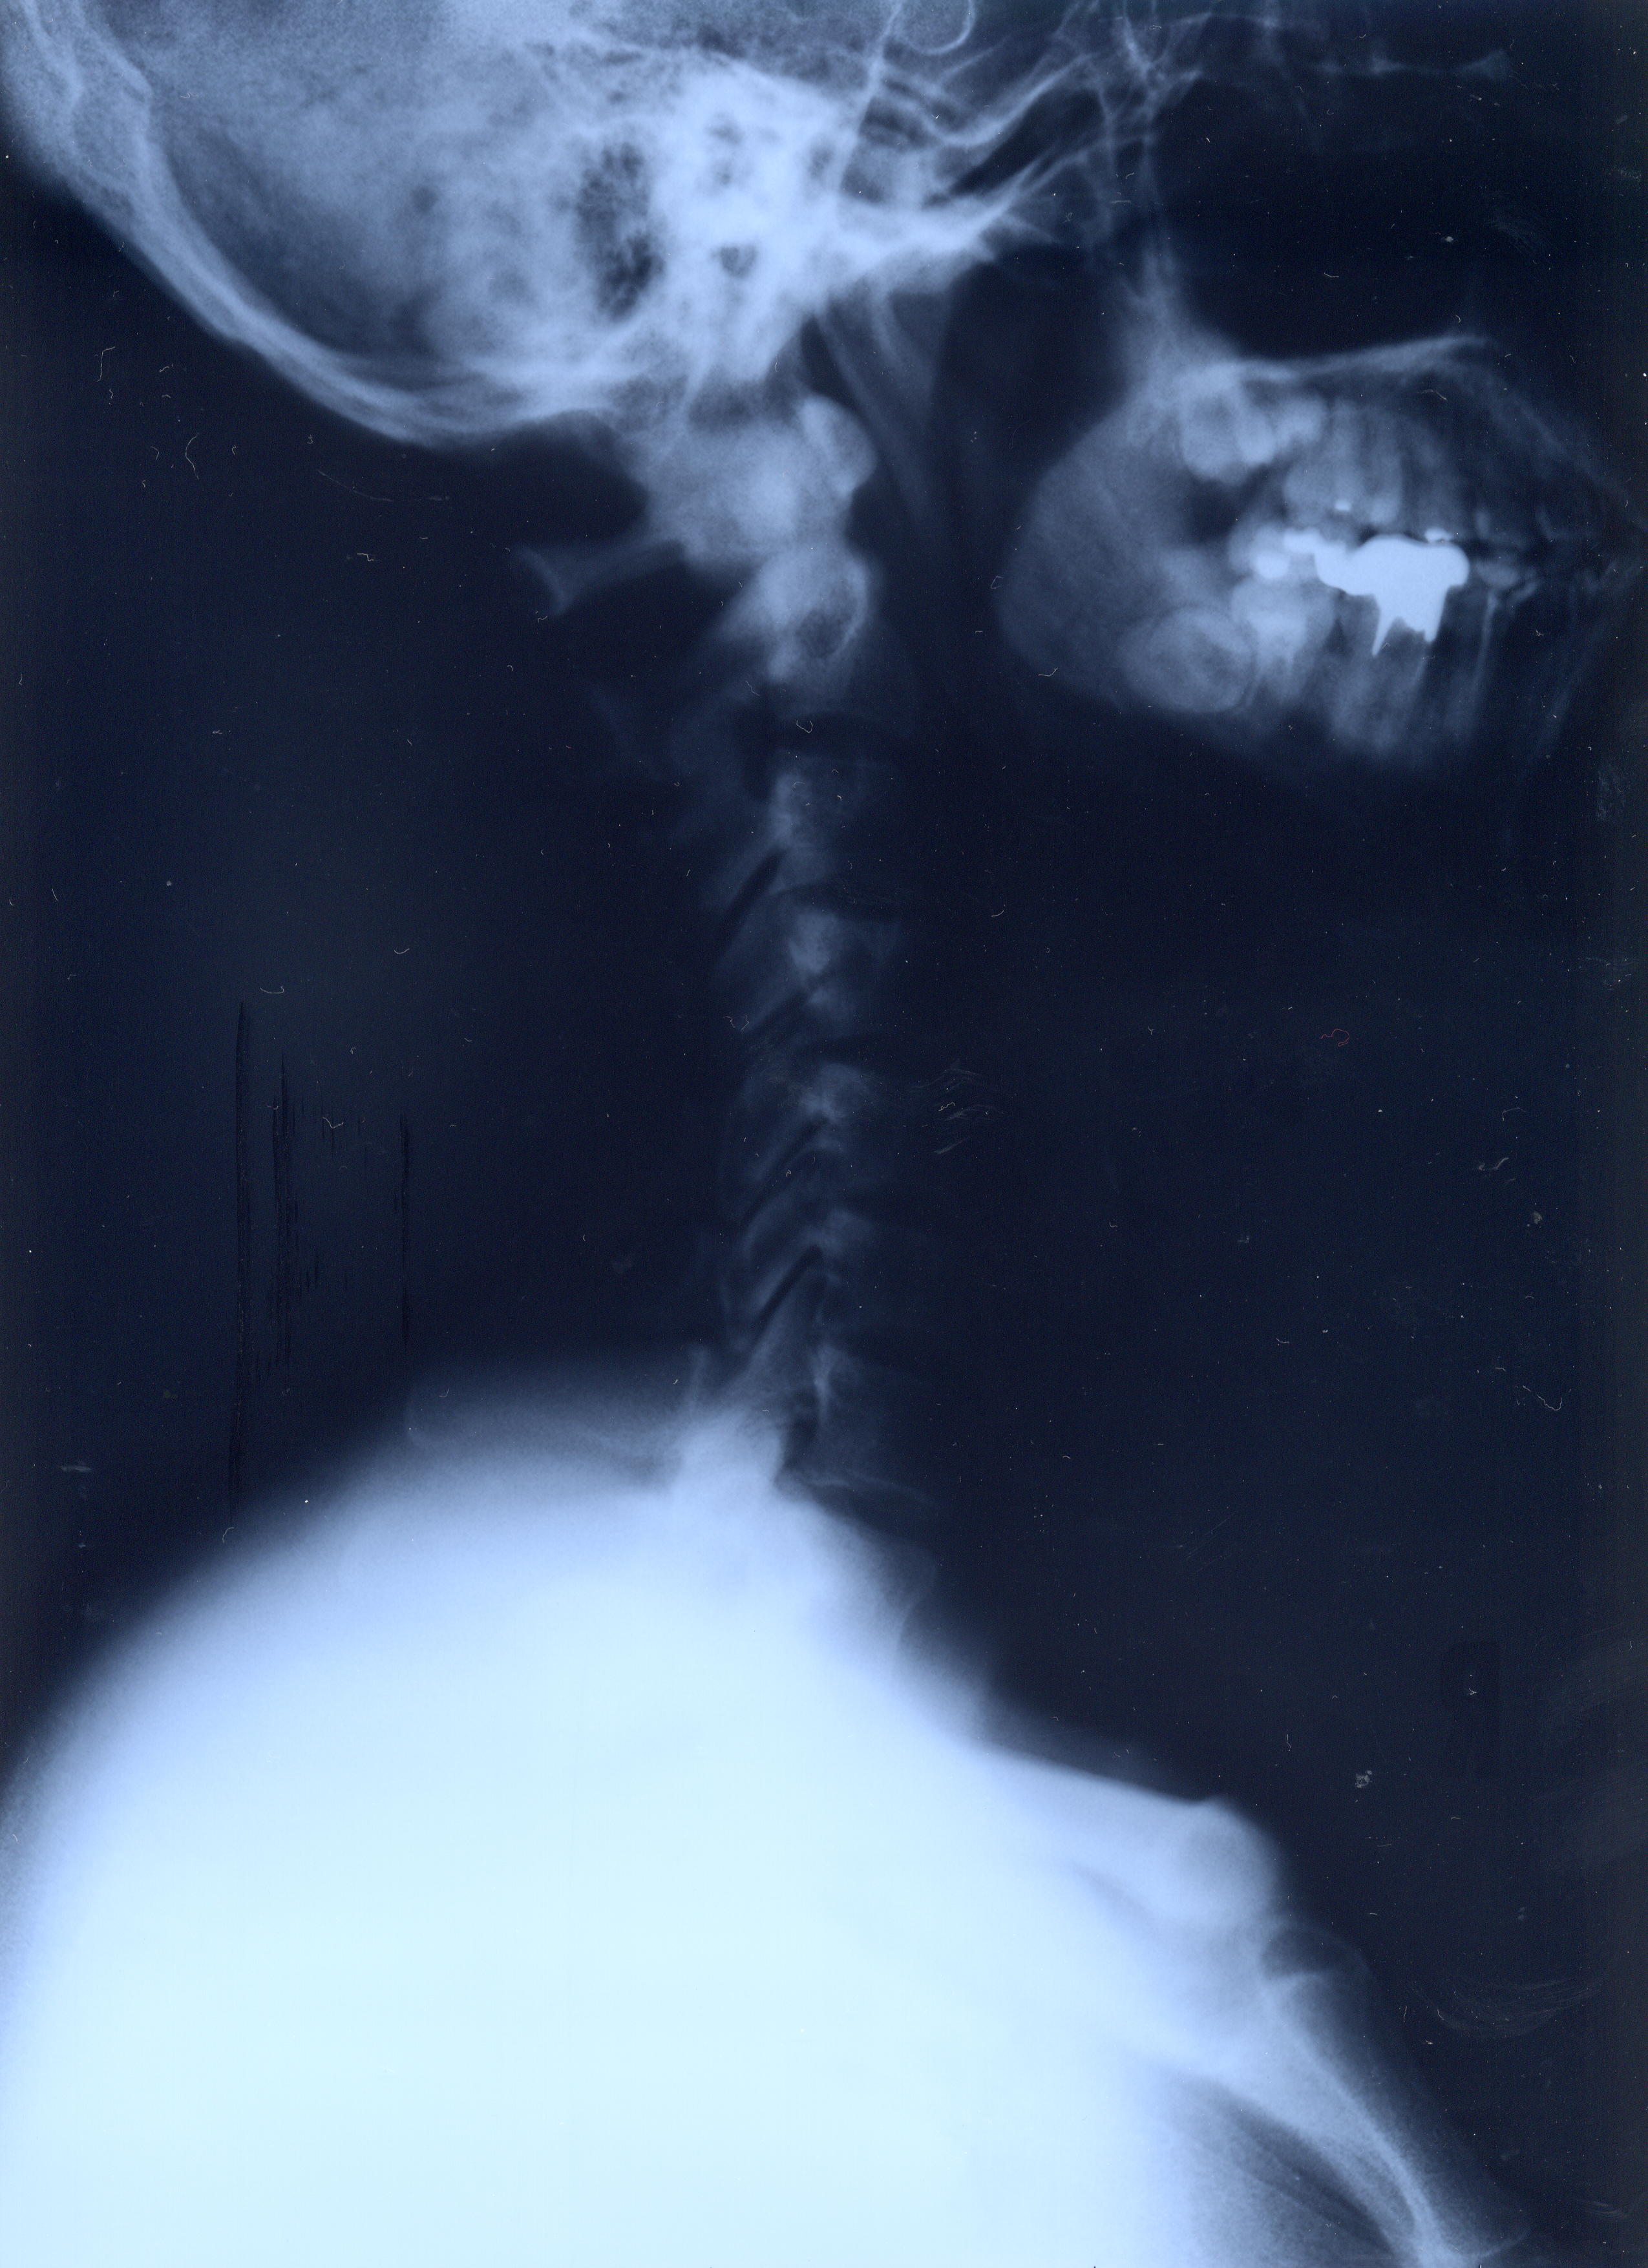

@@Ž„‚Μ”wœ‚Μ‚wόŽΚ^‚Ε‚·@@˜‚ͺ’Ι‚­‚Δ’Ι‚­‚āII@2002/1/22ŽB‰e

‚QD˜‚Μ‰‘@@Šg‘ε